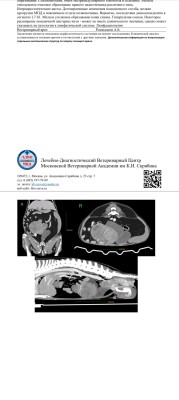

КТ брюшной полости

Дополнительно : в области гипогастрия масс-эффект 124,2*97,5 мм( точный размер определить затруднительно ), эхогенность смешанная, эхоструктура неоднородная за счет наличия множественных полостей неправильной формы с анэхогенным и гипоэхогенным содержимым, васкуляризация выражена, локально по периферии стеатит .

-новообразования гипогастрия( с учетом анамнеза предположительно семенник)